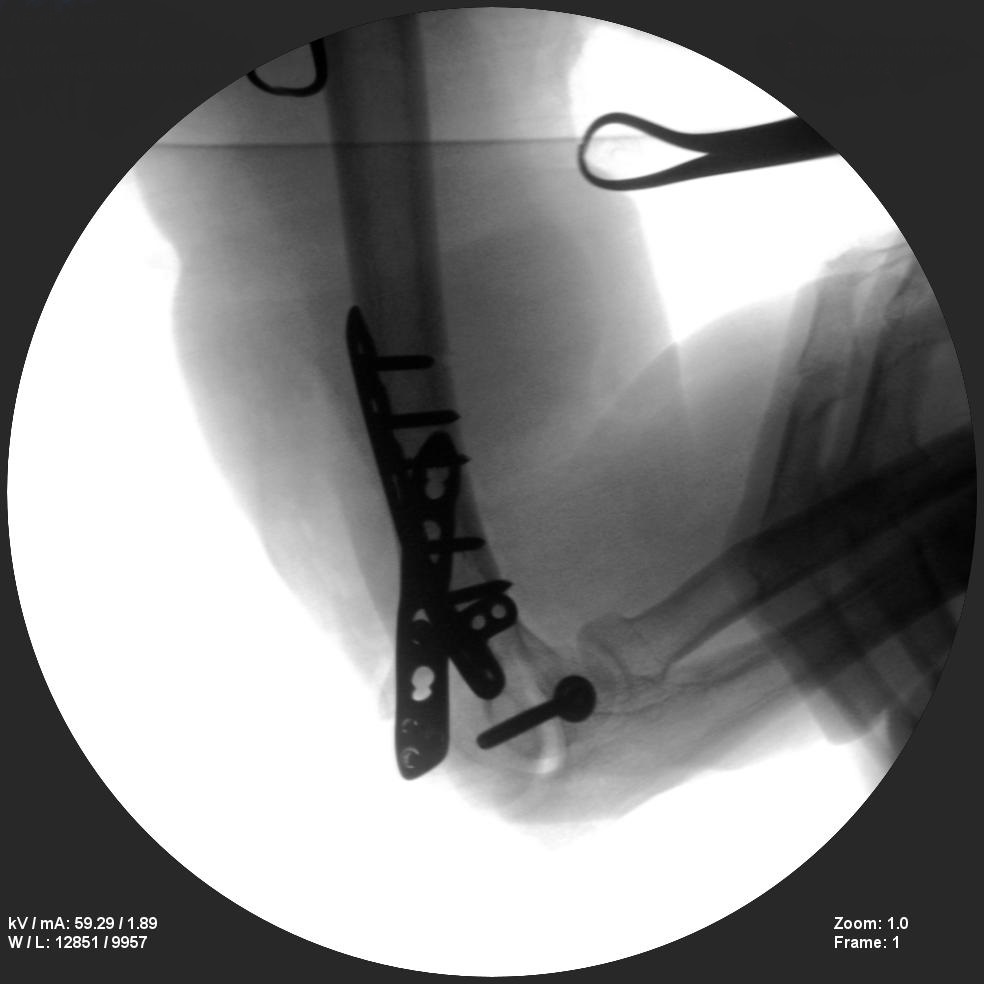

ORIF - Open reduction internal fixation

Long bone nailing